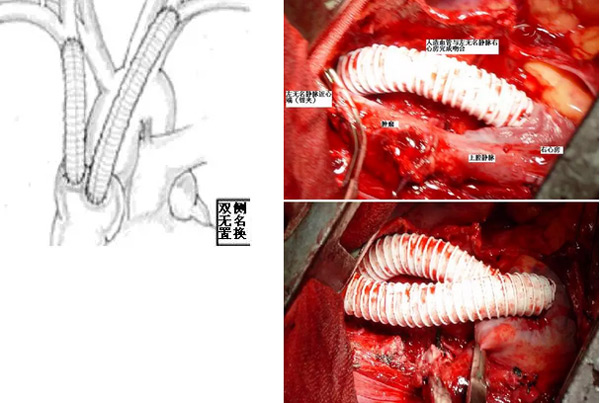

山东省立医院东院胸外科采用一侧无名静脉与右心房吻合通血,再完成肿瘤及受累上腔静脉的切除,再完成另一侧无名静脉与上腔静脉近心端的吻合,或仅吻合一侧无名静脉与左心房。这样整个手术过程不存在上腔静脉阻断的问题,从而避免了该类手术最大的风险,即脑缺血。

(2)人造血管分别与左、右无名静脉及右心耳、右心房吻合,上腔静脉无阻断

(3)人造血管与右(或左)无名静脉及右心耳吻合、左(或右)无名静脉结扎,上腔静脉无阻断